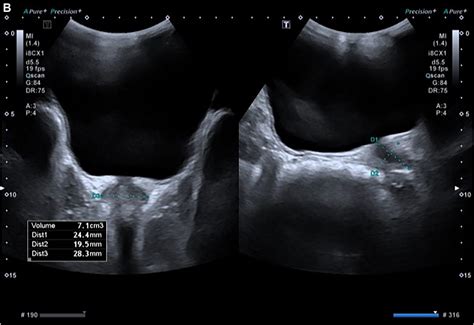

Medical ultrasound visualization of the prostate gland

To accurately determine if an individual’s prostate falls within a normal prostate volume range, medical professionals employ specific diagnostic tools. These imaging techniques provide precise measurements that are far more reliable than a digital rectal exam alone. The common methods include:

Transrectal Ultrasound (TRUS) The gold standard for measuring exact dimensions (length, width, and height) to calculate volume.

• normal prostate volume ultrasound